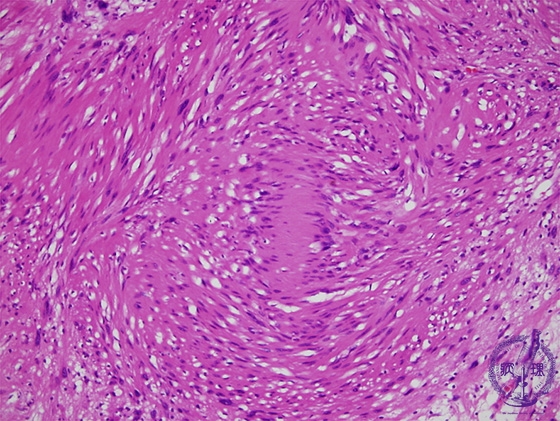

Microscopic findings (H.E. high power view): In Antoni A area, ball-like fibrous bundles with bipolar nuclear palisading, termed Verocay bodies, are also identified (red circle).

Click the image to see the enlarged image.